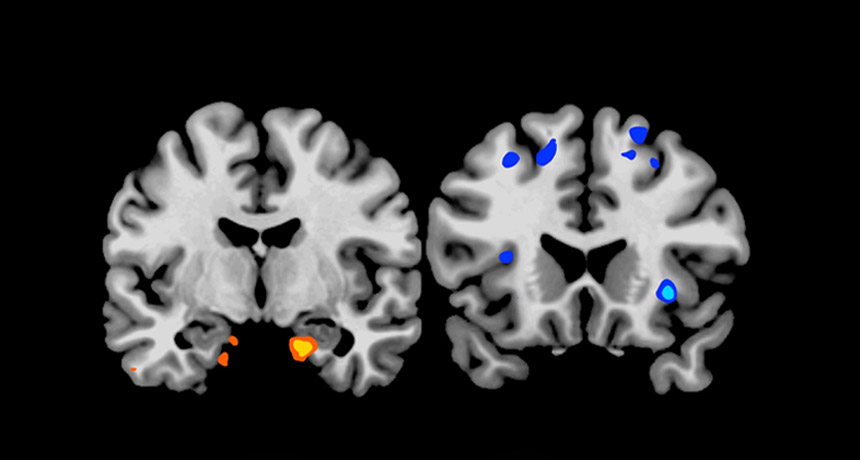

MMM, DOUGHNUTS When confronted with a picture of junk food, people who pulled all-nighters had boosted activity in the amygdala (left), a brain structure associated with the desire to eat, and reduced activity in regions of the cortex (right), which have been tied to food evaluation.

Matthew Walker et al.